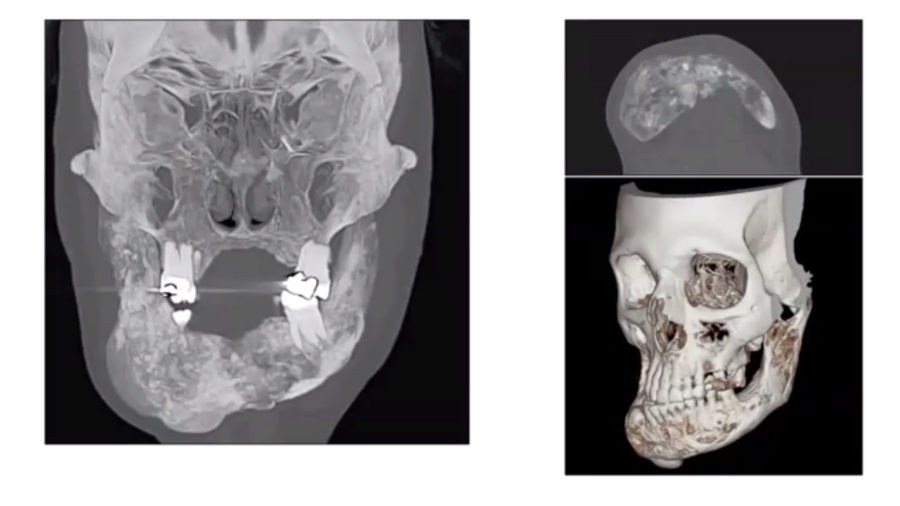

Pre-reconstruction planning: patient and defect evaluations

As the specific details of flap use depend on both the patient and the defect, it is essential to evaluate both carefully. A patient evaluation includes general status, including age and any comorbidities, their oncologic prognosis (including life expectancy), their aesthetic expectations (which may require some management), and the degree of support available to them if discharged to home.

Defect evaluation begins with the location. After the resection of the necessary tissues, will all wounds be hidden inside the mouth? Which type of tissue (muscle, bone, skin) will need to be replaced? Will it be necessary to wait for any infections to clear before proceeding with surgery? Is it possible to estimate a healing time? And, following radiotherapy, will the surrounding tissue be adequate to support a flap or other corrective structure?

Preparing for major oral reconstruction

Once the relevant patient and defect characteristics are understood, reconstructive options can be considered. If not enough tissue will be available inside the mouth, e.g., for a local flap, where will the tissue come from? Does the prospective donor site include a good-quality pedicle? If not, how will blood reach the flap? And especially, as a surgeon, do you and your team have the expertise to perform this procedure?